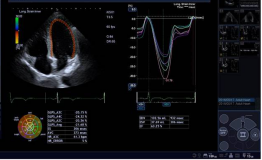

10. 全面的心脏应用:Aplioi900可为临床提供全方位心脏超声解决方案,支持专业的经胸心脏探头及经食道探头。

1) 二维/三维室壁运动追踪技术 (2D/3D Wall Motion Tracking)

2) 心脏容积成像